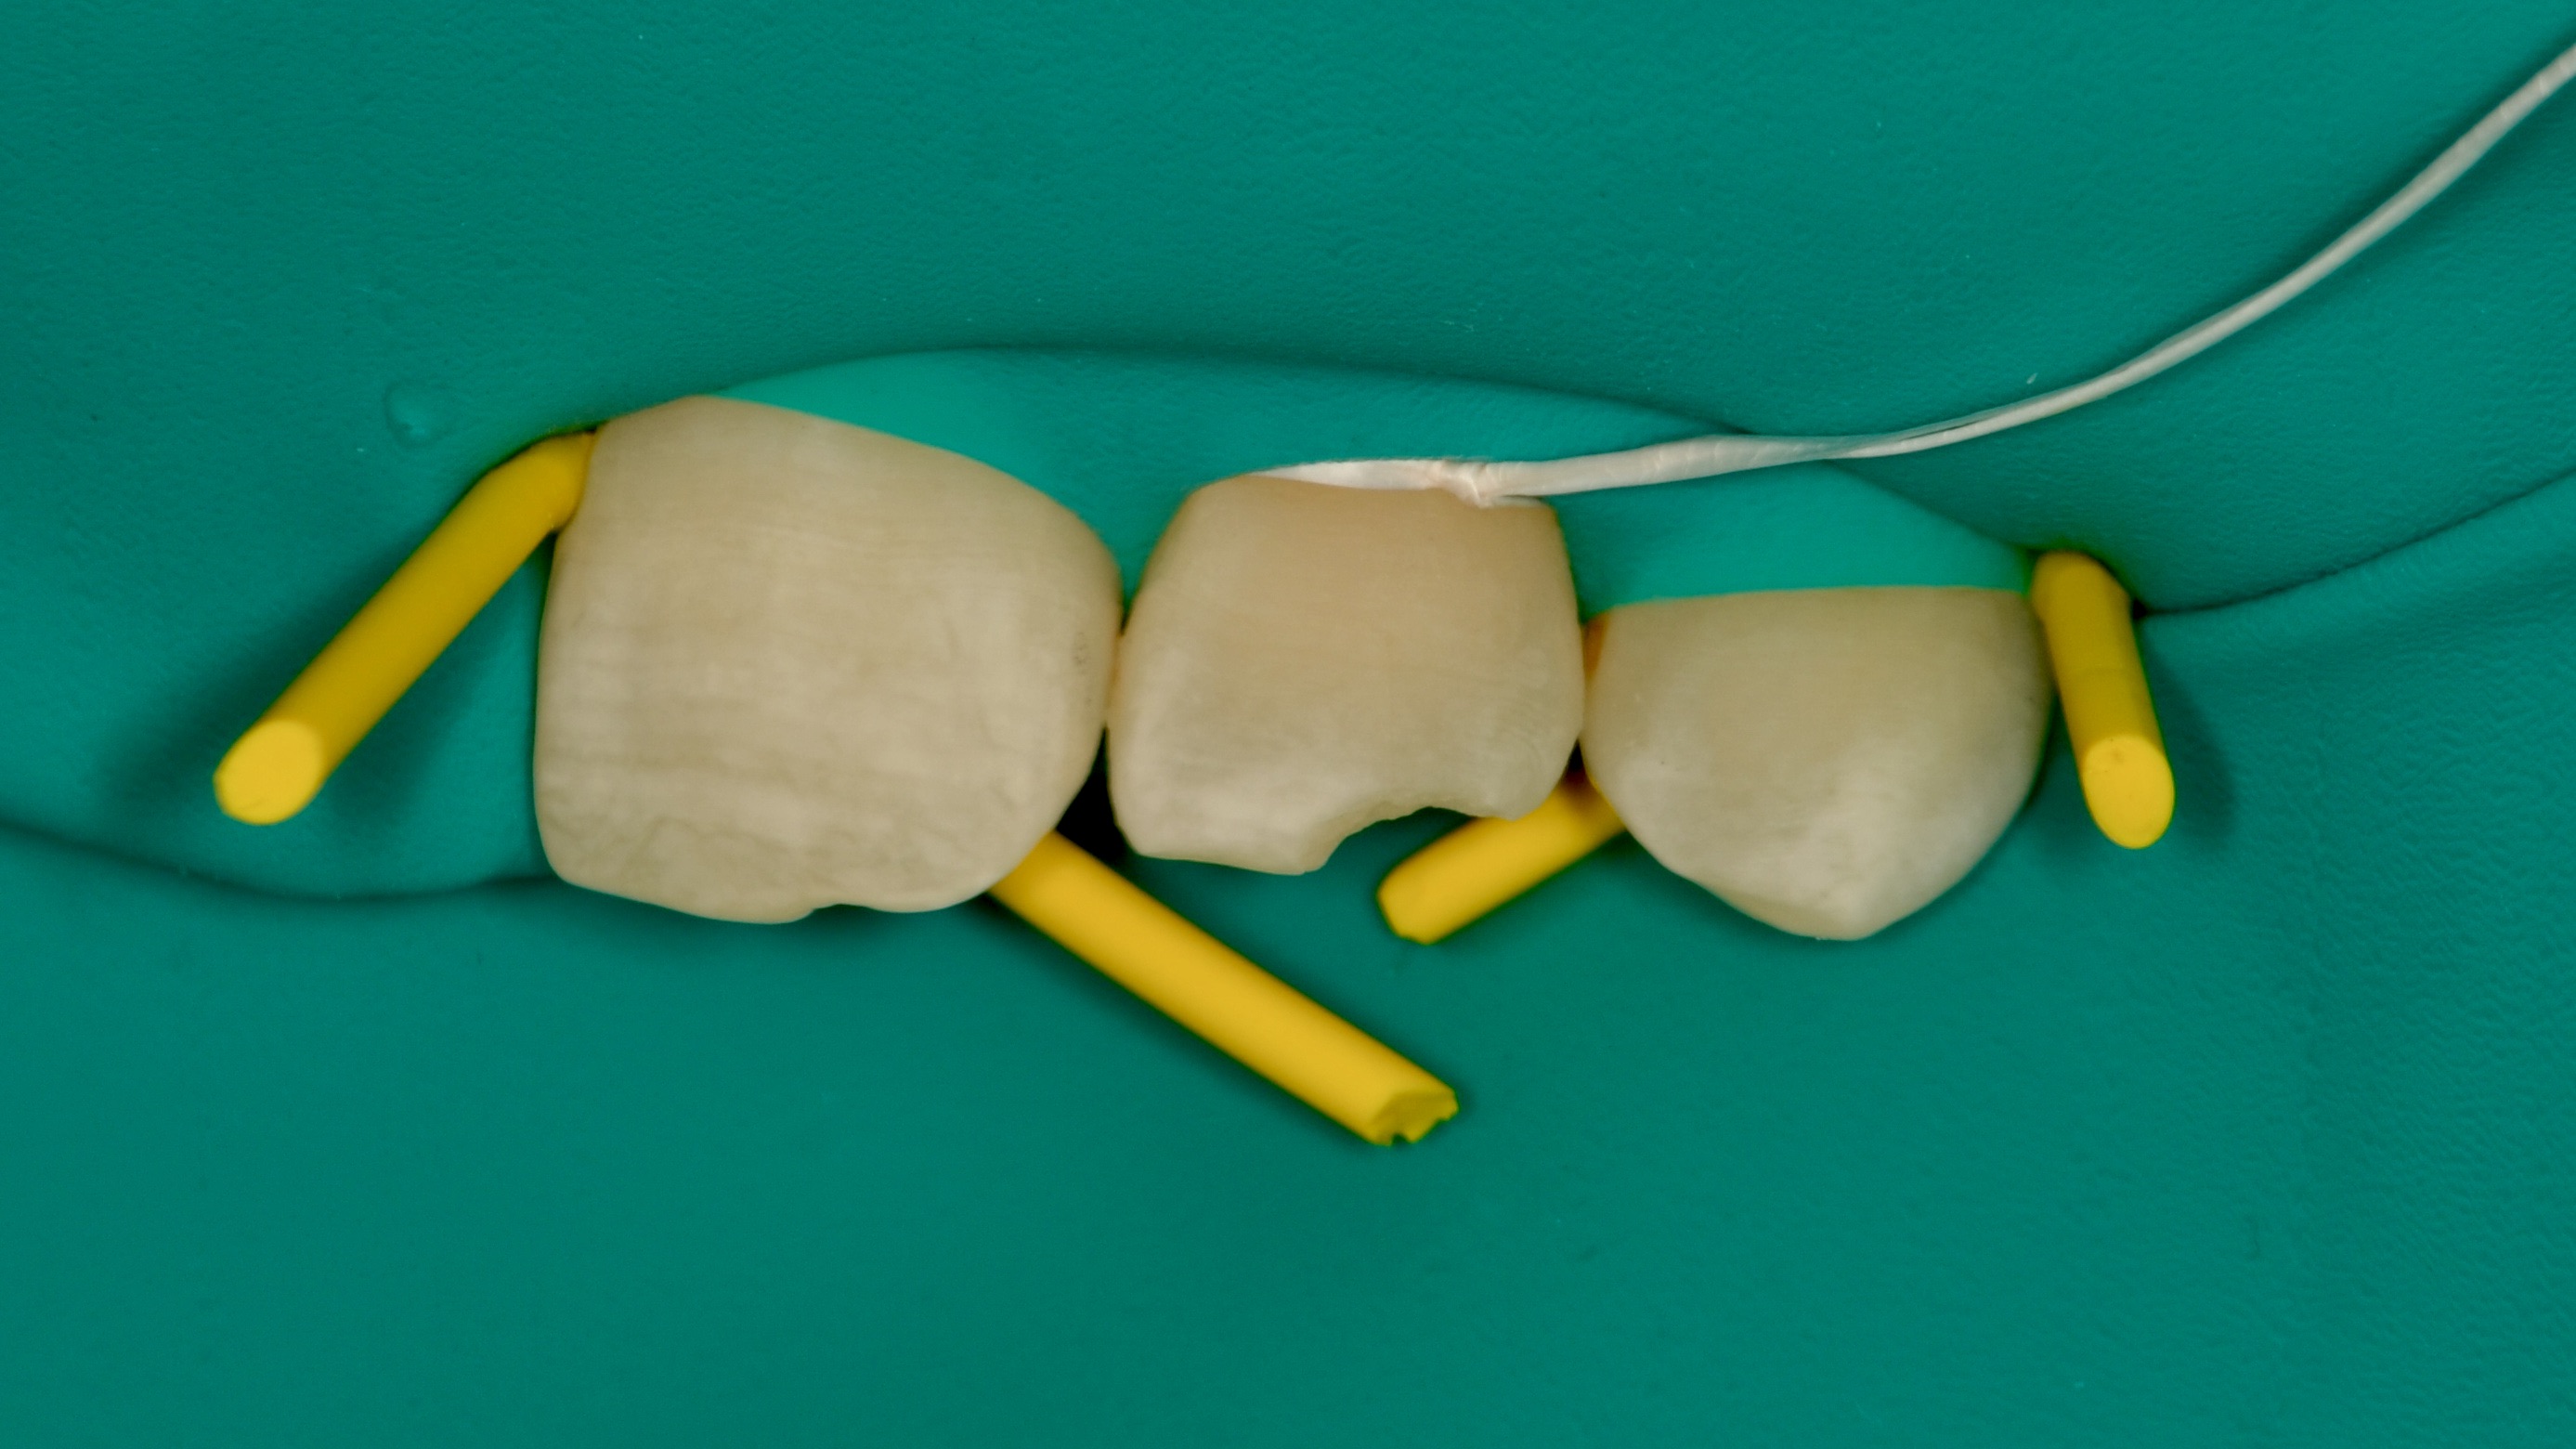

Custom Ceramic Crown